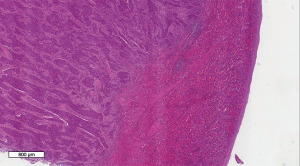

A 40-year-old male with a significant history of smoking presented to the clinic with an enlarged cervical lymph node. The initial clinical impression was lymphadenitis, for which appropriate treatment was administered. However, the patient showed no clinical improvement following therapy. Consequently, an ultrasound examination was performed, revealing multiple enlarged cervical lymph nodes. A true-cut biopsy revealed metastatic poorly differentiated carcinoma. Comprehensive imaging studies, including computed tomography (CT) scans of the head, neck, chest, abdomen, and pelvis, as well as magnetic resonance imaging (MRI) of the head and neck and a single-photon emission computed tomography/positron emission tomography (SPECT/PET) scan, were performed. Together with the physical examination and laboratory findings, the patient was diagnosed with NPC, staged as T3N2M0. Serology for Epstein Barr virus was performed, which was found to be positive. Based on these findings, and following multidisciplinary discussion in the Head and Neck Tumor Board, the patient was planned for concurrent chemoradiotherapy consisting of weekly cisplatin and radiotherapy (70 Gy in 33 fractions). During the course of treatment, the patient developed severe mucositis, significantly impairing oral intake, necessitating the placement of a percutaneous endoscopic gastrostomy (PEG) tube for nutritional support. Post-treatment whole-body MRI and PET/CT imaging demonstrated regression of the primary disease with residual uptake in the retropharyngeal lymph nodes, along with new osseous lesions involving the right iliac bone, right femoral head, and pubic bone. A bone biopsy from the right pelvic bone confirmed metastatic involvement. The patient was subsequently started on systemic chemotherapy with weekly paclitaxel/carboplatin and capecitabine. Following six cycles of chemotherapy, repeat PET/CT imaging showed persistent bone metastases and stable mild uptake in the left nasopharyngeal region. Given the extent of bony disease, SBRT was not pursued, and systemic therapy was switched to gemcitabine. Subsequent PET/CT imaging revealed disease progression with new involvement of abdominal lymph nodes. As a third-line approach, the patient was initiated on pembrolizumab, administered every three weeks for a total of (38 cycles) and received stereotactic body radiotherapy (SBRT) to retroperitoneal abdominal metastases (5 fractions). During the course of treatment, the patient developed additional metastatic sites, including a paraspinal mass and axillary lymphadenopathy, for which local radiotherapy was administered. On surveillance follow-up, the patient reported intermittent left-sided abdominal pain. Further evaluation with PET/CT of the abdomen and pelvis revealed a splenic lesion, raising concern for disease progression. These findings were confirmed with MRI of abdomen. A tumor board was formed in the hospital where the team discussed the case thoroughly to make a final diagnosis and a decision. The board agreed to perform splenectomy for diagnostic and therapeutic purposes. There was a mutual agreement between members of the tumor board and the team preferred to have a laparoscopic splenectomy for diagnostic and therapeutic purposes rather than an open laparotomy. Patient was given pneumococcal, meningococcal, and Haemophilus influenzae vaccines prior to the procedure. Patient underwent laparoscopic splenectomy and distal pancreatectomy with no complications. After performing the procedure, the specimen was sent for histopathology and a week later, his pathology results came out that confirmed metastasis from NPC as a primary origin. Histopathological examination of the splenic lesion revealed subcapsular replacement of the normal splenic parenchyma by metastatic neoplasm (Figure 1). The neoplastic cells exhibited moderate eosinophilic to amphophilic cytoplasm, round nuclei, and prominent eosinophilic nucleoli, arranged in sheets (Figure 2). Keratinization was absent, and a prominent lymphoplasmacytic infiltrate was noted surrounding the tumor cells (Figure 3). Immunohistochemistry showed strong and diffuse membranous and cytoplasmic positivity for cytokeratin 5/6 (CK5/6) and strong nuclear positivity for P63 in the neoplastic cells (Figures 4,5). In situ hybridization for Epstein-Barr virus (EBV-ISH) demonstrated strong and diffuse nuclear positivity, confirming EBV association (Figure 6). The patient was kept under observation for several months. Follow-up imaging subsequently revealed new metabolic activity in the stomach. A biopsy of the gastric lesion confirmed metastatic disease. As a result, systemic therapy with carboplatin in combination with pembrolizumab was reinitiated. Due poor general status of the patient and advanced unresponsive disease the treating team kept him on palliative treatment of chemotherapy and radiotherapy. All procedures performed in this study were in accordance with the ethical standards of the institutional and/or national research committee(s) and with the Declaration of Helsinki and its subsequent amendments. Written informed consent was obtained from the patient for the publication of this case report and accompanying images. A copy of the written consent is available for review by the editorial office of this journal.